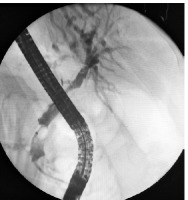

We used an ultra slim gastroscope with a diameter of 5.7 mm (PENTAX Medical, EG17-i10) and a working channel of 2.0 mm. During the procedure we used CO2 insufflation. After performing a re-papillotomy and papilla balloon dilation, we accessed the common bile duct using the “J” manoeuvre. After ascending to the common hepatic duct, the obstructed stent and the scarring of surrounding tissue were visualised (Figure 1). Using an APC probe (Figure 2) in a sweep motion (cranial to caudal), we made about 10 passes, creating a 3 mm wide passage though the stent’s lumen. Next, we used an RFA catheter to further ablate the stent lumen – we used an 18 mm RFA catheter (ELRA, StarMed) and the stent lumen was ablated for 2 min per pass (3 passes made in total to cover the full length of the stricture) with 10 Watts and 80°C (Figure 3). After that, a plastic biliary stent was passed through the metallic stent to prevent restenosis (Figure 4).